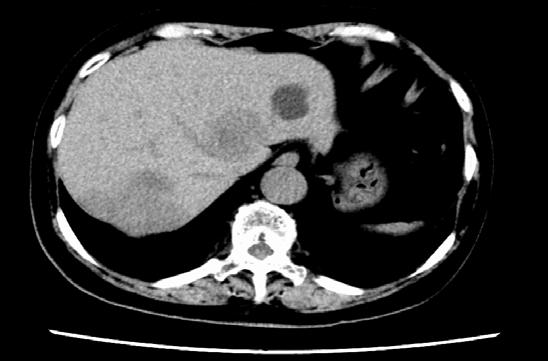

100 The Two Faces of Hepatocellular Carcinoma: Navigating Cancer Care and Liver Health

E Kaplan